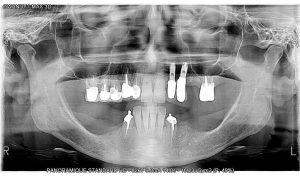

EXCEPTIONAL IMAGE QUALITY

You’ll be able to view all clinical and anatomical details with maximum precision.

Specially adapted programmes

The I-Max features a wide range of programmes that can be used for any type of examination your practice requires (child / adult).

Incorporating ALI-S (Automatic Layers Integration System), the unit directly and automatically selects the best sections in order to display a perfect image, without any form of operator involvement.

24 2D programmes to make your medical diagnostics easier.